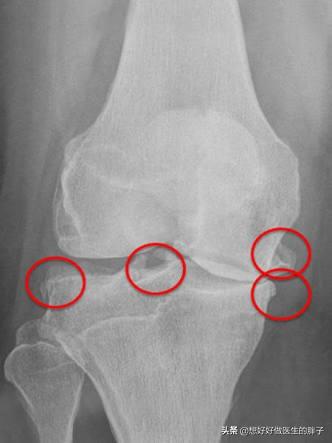

而如果膝关节问题比较严重,关节活动已经出现了明显的受限,关节软骨磨损的特别严重,那么应该进行膝关节置换手术,帮助患者解决疼痛的问题以后再进行更加系统的康复锻炼,尽量帮助患者恢复到日常生活当中去,比如像下图这样的x线,表现患者关节腔内的软骨可能已经磨损消失殆尽了,这种情况如果患者疼痛比较严重,进行关节置换是最好的选择,否则患者膝关节疼痛、酸疼、无力的症状很难改善。